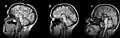

- Image du corps calleux en coupe sagittale(plan vertical, orienté d'avant en arrière) en IRM (imagerie par résonance magnétique).

IRM révélant une agénésie du corps calleux.